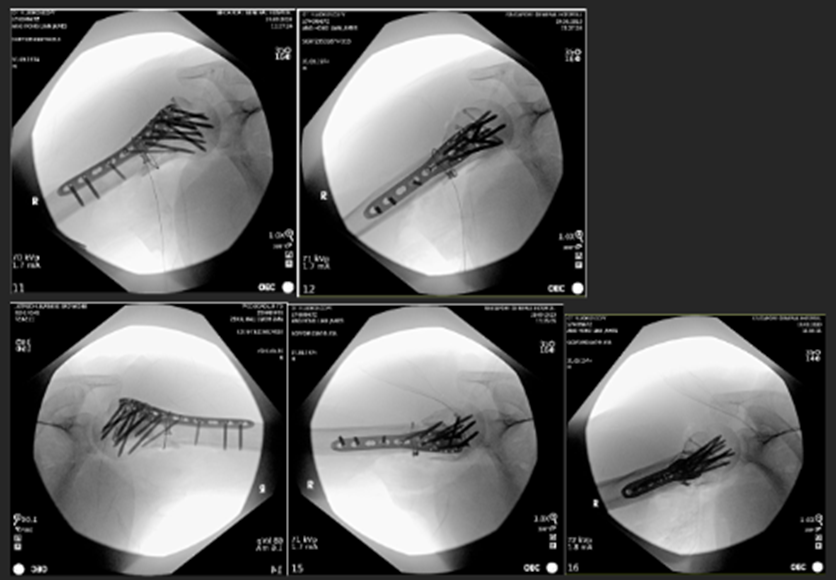

Image 3: Immediate postoperative radiographs of the right shoulder.

A. Anteroposterior (AP) view

B. Valpeau view

C. Lateral/ Y scapula view